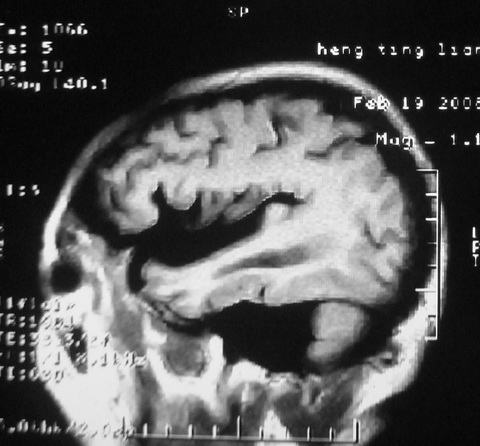

m,72,头疼,头晕两年,伴视力模糊三月,饮食呛咳两天。pe:颈部抵抗,左眼突出,左眼瞳孔约3mm,对光反射消失,双眼失明,伸舌困难,双肺呼吸音粗,心率110次/分,左上肢肌力i级,左下肢屈曲,肌张力高。现有08年2月19mri平扫及10年2月8日mri增强请会诊。ct病灶呈低密度伴散在点、片状等密度区,无明确钙化(无ct片资料可供上传)。[

脑外肿瘤,表皮样囊肿可能性大。

考虑表皮样囊肿。

脑外肿瘤,病灶呈匍匐蔓延,表皮样囊肿可能性大。

脑外肿瘤,病灶呈匍匐蔓延,表皮样囊肿可能性大。支持!